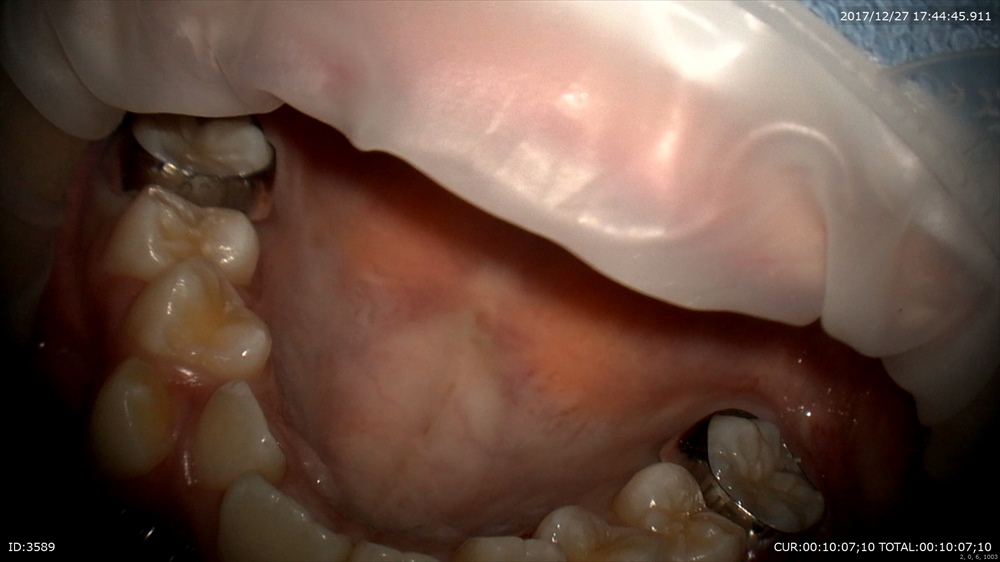

次の患者さまは精密根管治療

ラバーダムで準備

結構汚れています

綺麗にします。根管内の細菌がぐっと減りました。